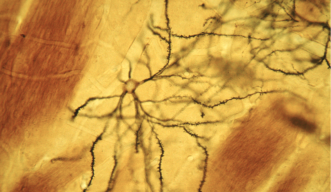

沖縄科学技術大学院大学(OIST)で行動の脳機構ユニットを率いるアーバスノット教授は、英国アバディーン大学の博士課程で生理学専攻の学生であった時に、スウェーデンの研究グループが発表した論文に出会い、一般に快楽を司る脳内化学物質と呼ばれる神経伝達物質のドーパミンに興味をもちました。その論文はルンド大学の研究グループのベンクト・ファルクおよびファルクの指導者であるニルス-オーケ・ヒラープらによって発表されたもので、脳内の神経伝達物質分布の可視化に初めて成功した方法について論じていました。この革命的な偉業によって、脳内化学物質伝達のメカニズムを調べる最初のツールが確立されたのです。

この時以来、アーバスノット教授のドーパミンへのこだわりが始まりました。OISTで、同教授のユニットはドーパミンを受け取るニューロンの構造や生理機能について調べており、脳内のドーパミンの役割を解き明かそうとしています。ドーパミンの性質は複雑で捕らえどころがないため、ドーパミンの機能不全によって生じる疾患を治療することは困難です。しかしアーバスノット教授は、1960年代半ばにドーパミンと出会ってからずっと、その解明に努めてきました。